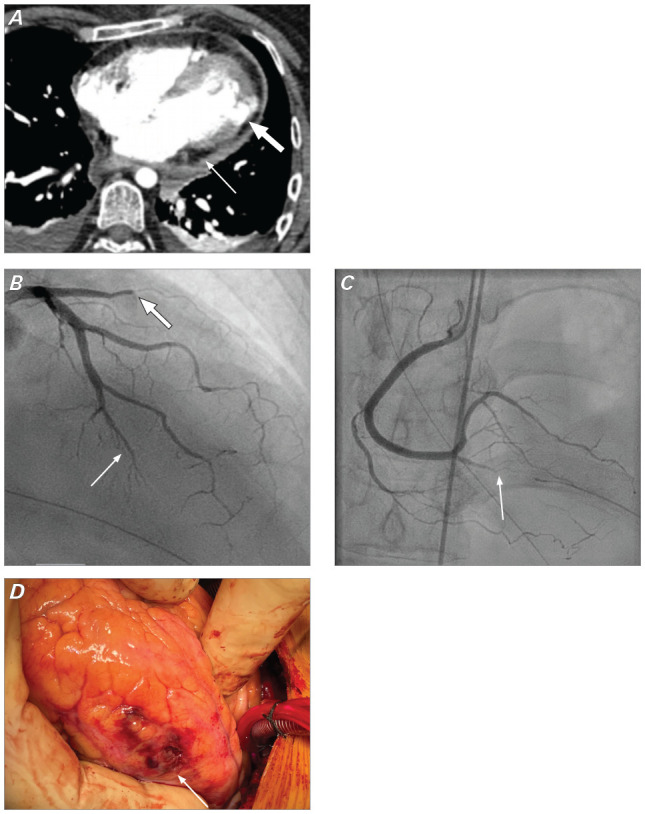

左心室游离壁破裂是心肌梗死的致命并发症。尽管紧急手术修复是首选治疗方法,但修复方法仍高度个性化。本报告介绍了一例特纳综合征患者自发性冠状动脉夹层导致左心室游离壁破裂的病例,该患者在心肺旁路手术中使用 EVARREST 纤维蛋白密封补片无缝合技术成功修复了左心室游离壁。

Left ventricular free wall rupture is a lethal complication of myocardial infarction. Although emergent surgical repair is the treatment of choice, the method of repair remains highly individualized. This report presents a case of spontaneous coronary artery dissection in a patient with Turner syndrome that led to left ventricular free wall rupture and was successfully repaired on cardiopulmonary bypass using a suture-free technique with the EVARREST Fibrin Sealant Patch.